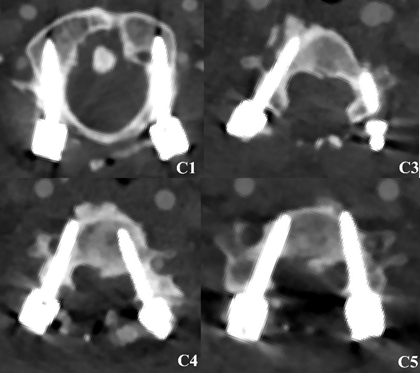

术后患者复查椎弓根螺钉位置安全,与术前设计一致,患者瘫痪症状明显减轻,达到了手术目的。

术后CT显示螺钉位置安全、准确